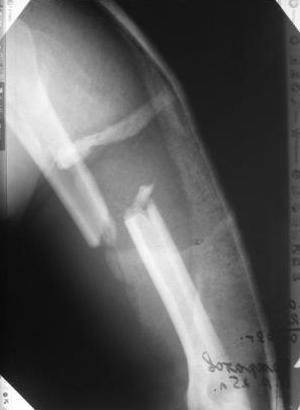

Какие Вам нужны конкретные ситуации... ведь диагноз есть, Р-снимки представлены... я выссказал свое мнение относительно штифтования... это и так предусматривает что у нас есть достаточное оснащение для этого ... какие еще ситуации нужны... наличие денег у пациента? или что???

Уважаемый товарисч.Данный перелом можно вылечить антероградным, ретроградным штифтованием, пластиной, аппаратом внешней фиксации, вытяжением за локтевой отросток на шине ЦИТО. Учитывая наличие тяжелой ЧМТ предпочтение должно отдаваться минимальноинвазивной технике.

Качество паредставленных Вами рентгеновских снимков крайне низкое, что косвенно свидетельствует об общей культуре работы в Вашем отделении.

Humerus.jpg

170KB (174189 bytes)